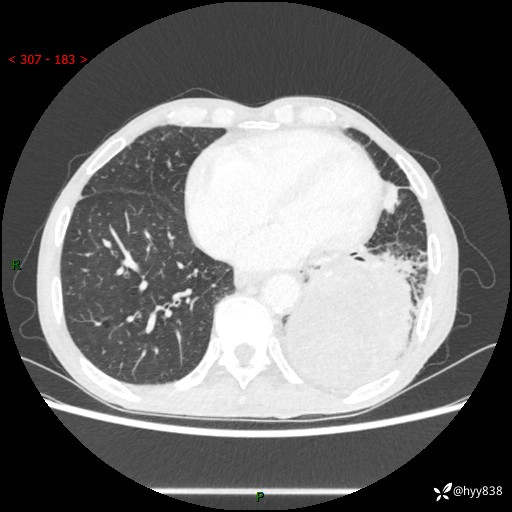

77岁/男,腹痛2月,CT发现左肺占位1天。巨大肿块,肺内或肺外来源…结果公布~

主诉:腹痛2月,CT发现左肺占位1天

现病史:患者于2025年9月间断左下腹胀痛,在当地镇卫生院行彩超检查考虑泌尿系结石,行止痛排石对症治疗未见明显好转;1天前腹痛症状加重,至当地市第三人民医院行CT检查:左肺下叶巨大团块状软组织影,考虑肿瘤性病变,建议增强CT检查;左侧胸腔积液;纵膈内淋巴结肿大;双肺肺气肿;右肺中叶纤维灶。为进一步求治,来我院就诊。

胸部CT平扫+增强